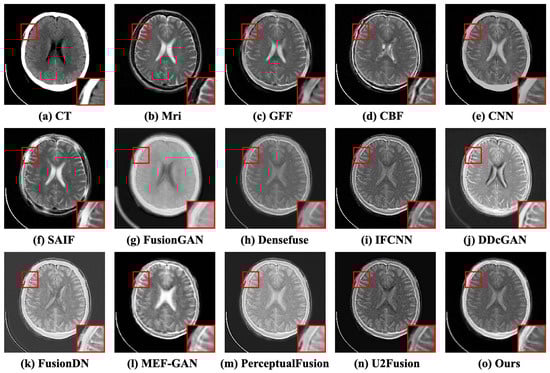

Case 3: Multiple infarctions. The third case is a 55-year-old male who suffered multiple refractory focal seizures in the setting of pulmonary empyema ([Online]. Available: http://www.med.harvard.edu/aanlib/cases/case34/case.html, accessed on 15 May 2023). The fused results of the subjective comparison for the third case are illustrated in Figure 9. The source MRI has more clarity and more tissue detail than the CT image, and it makes sense for both of the above pieces of information to be retained in the fused image. Nevertheless, these methods (e.g., GFF [10], CBF [11], and FusionGAN [35]) have weak visual contrast. There are distortions in the contours of images (e.g., SAIF [12], DDcGAN [21], IFCNN [15], and MEF-GAN [36]). In general, SAIF [12], DDcGAN [21], and CFGAN achieve superior perceived quality. Viewing the atrium in the red box, we can observe that CBF [11], SAIF [12], IFCNN [15], DDcGAN [21], U2Fusion [17], and CFGAN reserve more texture details. The six objective evaluation indicators are presented in Table 3. The proposed method CFGAN is proved to show better performance compared to the other twelve methods.

Figure 9.

The subjective comparison results of the third case. (a,b) represent the CT and MRI images. (c–n) denote the fused results of the competitors. (o) is the result of CFGAN.

Table 3.

The objective comparison results for the third case. The most prominent results are highlighted in bold.